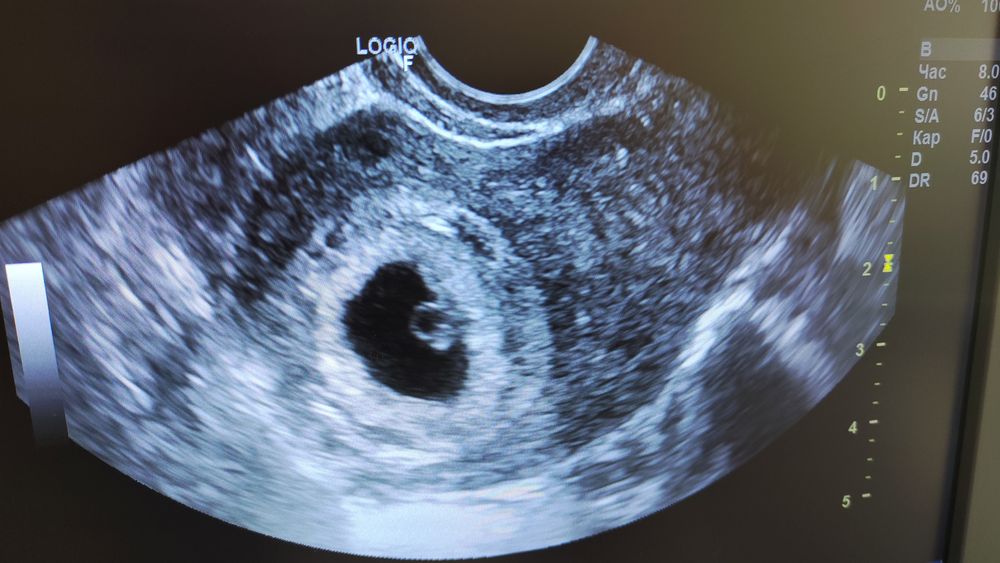

У меня в 6 недель был эмбриончик, но такой малюсенький, мне кажется, что если бы не аппарат УЗИ экспертного уровня, то точно ещё ничего бы не разглядели. Вот он маленький под желточным мешочком. Совсем ещё крошка. Я думаю, что вы просто рано пошли, да и оборудование смотря какое